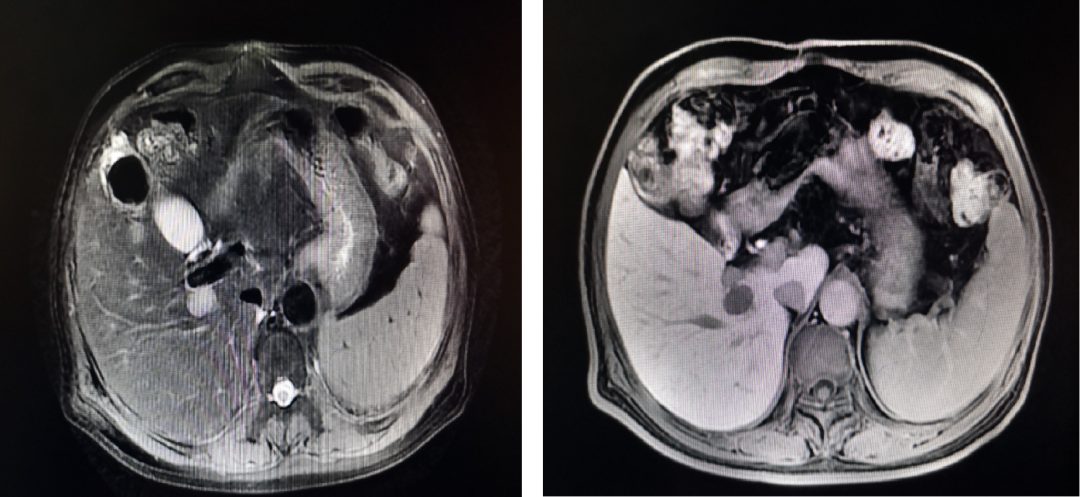

腹部CT及核磁提示紧邻右侧肝蒂约2cm实性占位,增强扫描呈现“快进快出”,符合肝细胞肝癌表现。测量肝体积,左半肝占标准肝体积(sFLR)的28.8%。

图示:PVE照片及PVE后8周肝脏增强CT